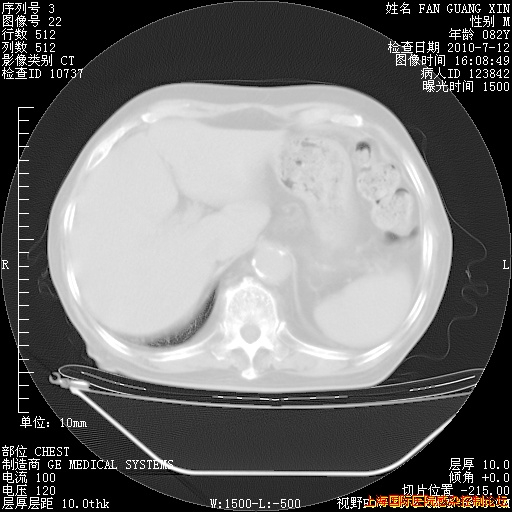

6月12日纵膈窗

整整相隔30天的肺部CT好像有所好转啊。甲强龙减量第3天,需要观察体温。

海管,自昨日你和我通完话后,不知您岳父消化道症状有无缓解?体温怎样?阅读7.12日胸部ct,个人认为目前激素治疗是有效的,甲强龙减量是适宜的。因在抗痨治疗,需密切观察肝功、肾功能和血常规。不过,老年、长期住院和大量使用激素,很担心菌群失调发生